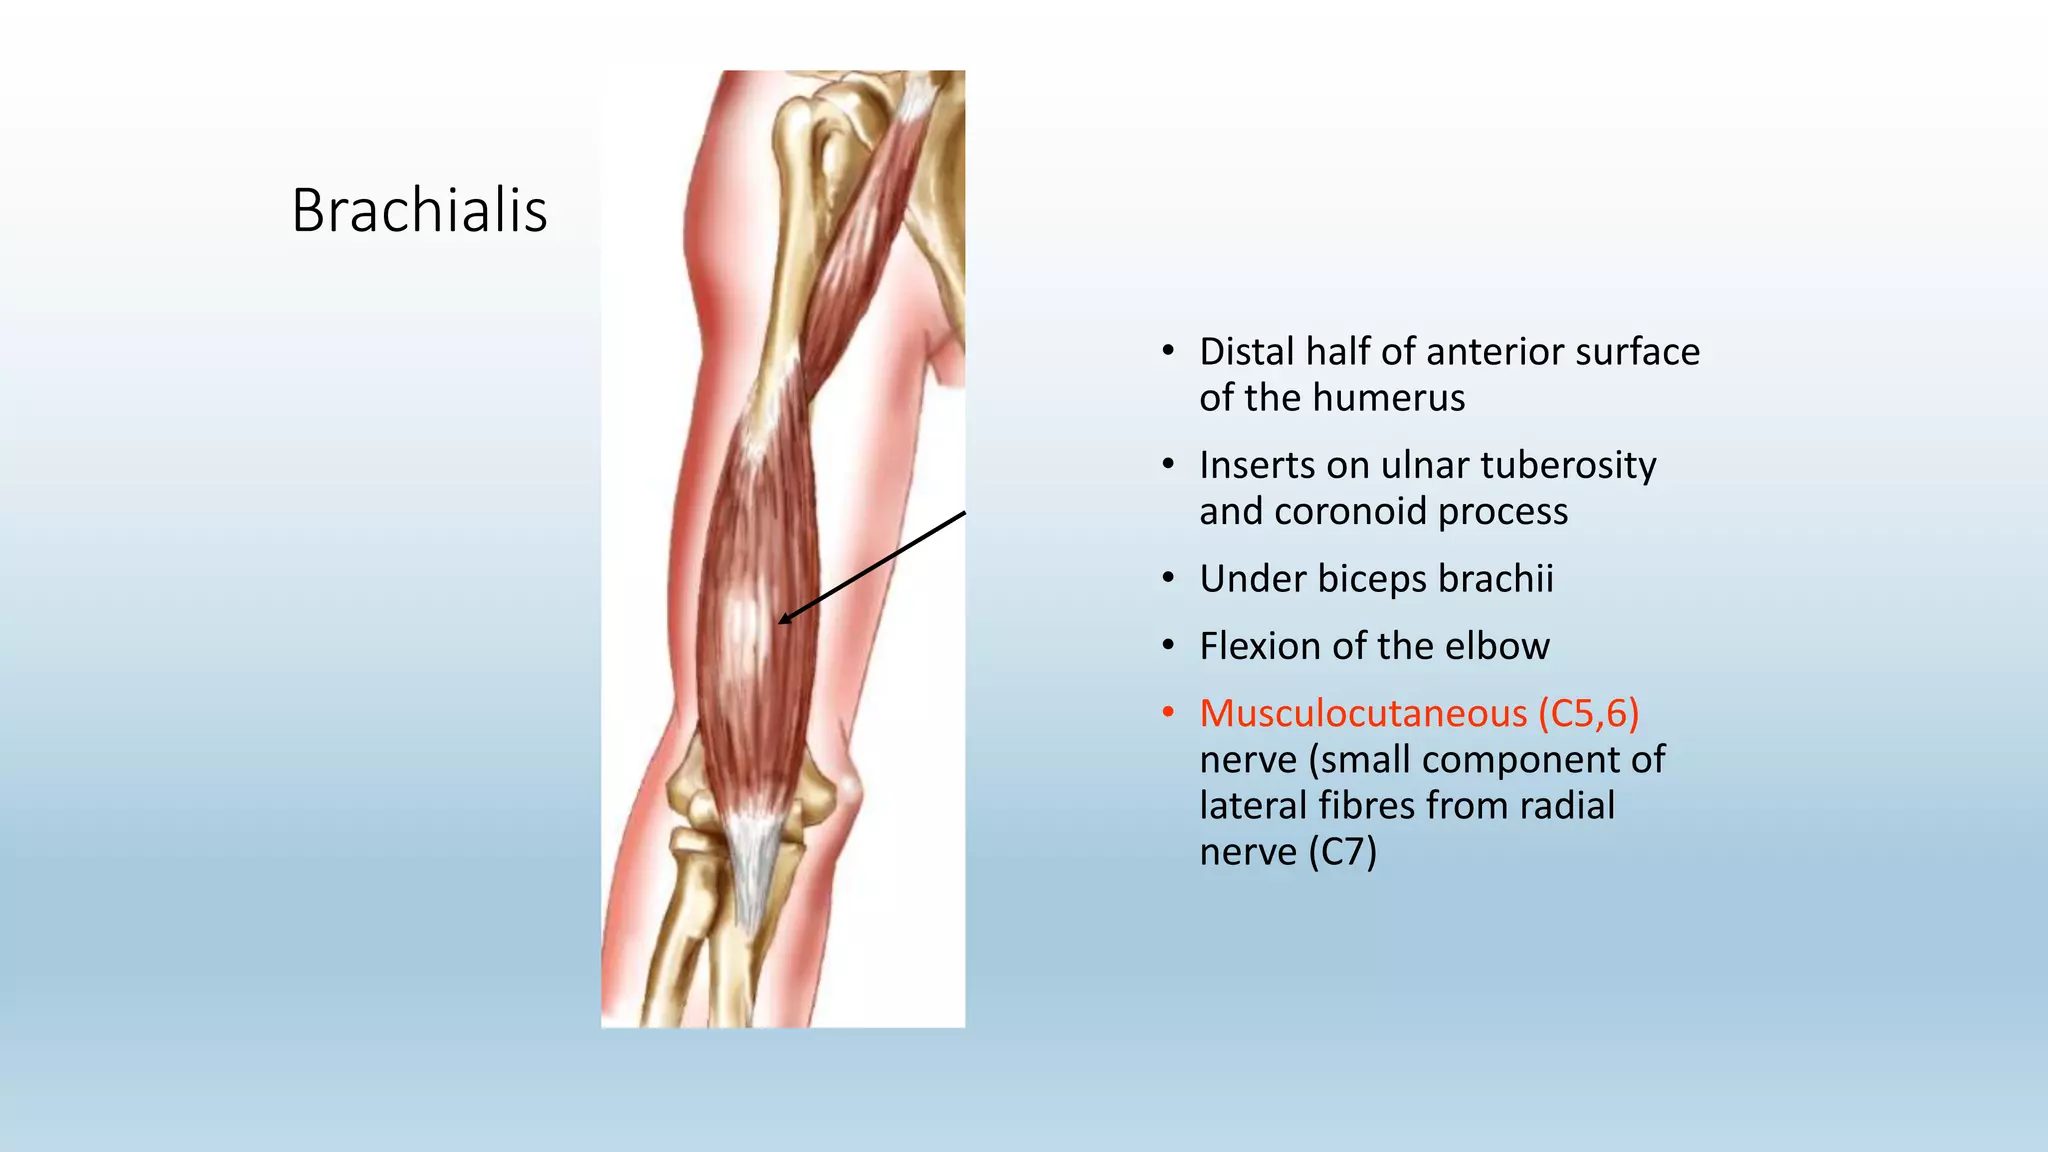

The document summarizes an anatomy revision session on the upper limb. It discusses various muscles of the upper limb including their origins, insertions, innervations and functions. Key muscles covered include the pectoralis major and minor, serratus anterior, deltoid, biceps brachii, brachialis, coracobrachialis, and triceps. It also discusses the rotator cuff muscles and muscles of the forearm including flexor carpi ulnaris and radialis. The session aims to help students identify upper limb muscles and understand their relations to nerves.